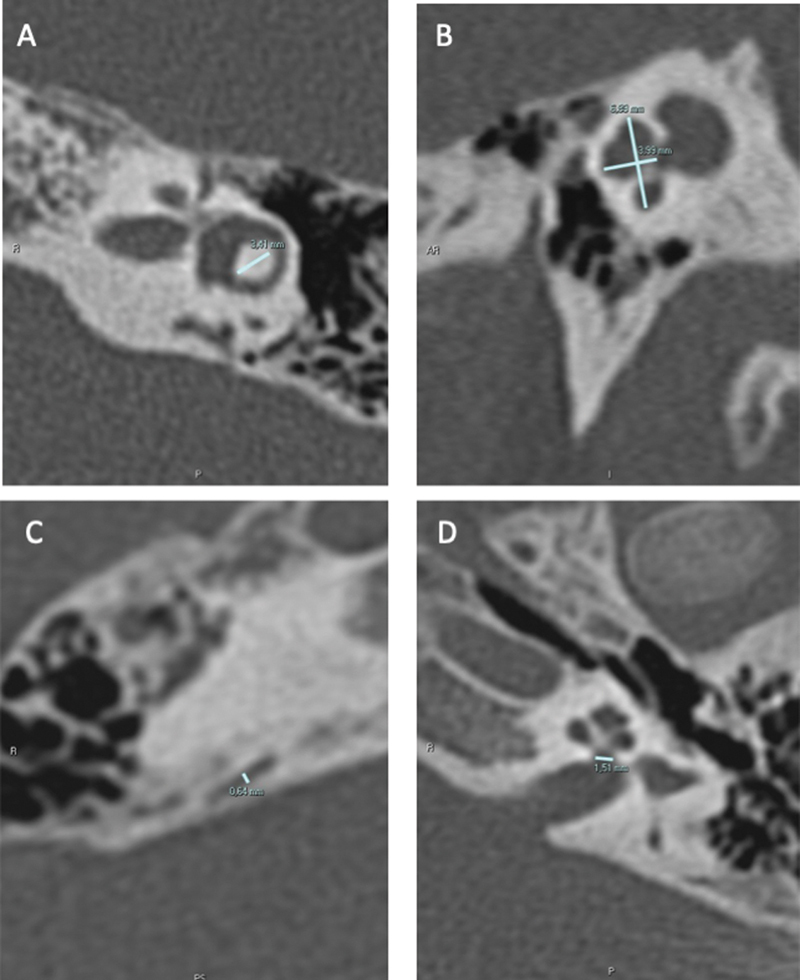

Introduction  One of the paths in the investigation of congenital sensorineural hearing loss (CSNHL) is to try to characterize its etiology through the inner ear evaluation using high resolution computer tomography (CT) scans. With minor malformation, it is not always possible for a simple visual inspection to recognize if the structure in the inner ear is normal or not. Objective  To verify if measurements of the inner ear are predictive of sensorineural hearing loss (SNHL) and suggest cutoff points of size limits. Methods  Retrospective cross-sectional study of inner ear CT scan measurements of 214 patients, 50 with congenital SNHL (CSNHL) and 164 acquired SNHL (ASNHL) (control group). Results  In the CSNHL group, central bony island (CBI) were 0.48 mm smaller ( p  < 0.001), cochlear nerve aperture was (CNA) 0.10 mm smaller ( p  < 0.001), and cochlea height was (CH) 0.15 mm smaller ( p  < 0.001). Vestibular aqueduct (VA) and cochlea width (CW) were similar between groups (0.70 vs 0.72, p  = 0.19, and 7.20 vs 7.15 p  = 0.23). The predictive cutoff points for CSNHL were CBI = 3.6 mm, CAN = 1.4 mm, CH = 3.4 mm, CW = 7.0 mm, and VA = 0.9 mm. Conclusion  Congenital sensorineural hearing loss determined a decrease in CBI, opening of the cochlear nerve (OCN), and CW. Thus, these measures, at the cutoff points indicated, should make us aware of the diagnosis of congenital hearing loss.